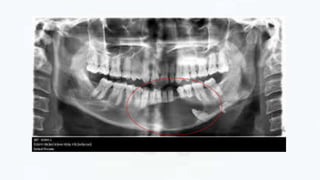

RADIOGRAGHIC FEATURES

• LOCATION

Most ameloblastomas (80%) develop in the molar ramus region of the

mandible

Most lesions that occur in the maxilla are in the 3rd molar area

• PERIPHERY

Well defined and frequently delineated by a cortical border

• INTERNAL STRUCTURE

Totally radiolucent

• EFFECT ON SURROUNDING STRUCTURES

 Causes extensive root resorption

 Tooth displacement common

 May cause extreme expansion of the mandibular ramus, and often

the anterior border of the ramus no longer visible in the panoramic

image